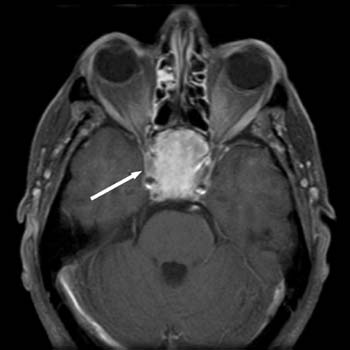

Chordoma is a rare slow-growing malignant neoplasm thought to arise from cellular remnants of the notochord. Chordomas can arise from bone in the skull base and anywhere along the spine. The two most common locations are cranially at the clivus and in the sacrum at the bottom of the spine.

There are three histological variants of chordoma: classical, chondroid and dedifferentiated. Chondroid chordomas appear to have a more indolent clinical course . In most cases, complete surgical resection followed by radiation therapy offers the best chance of long-term control. Incomplete resection of the primary tumor makes controlling the disease more difficult and increases the odds of recurrence.Chordomas are relatively radioresistant, requiring high doses of radiation to be controlled